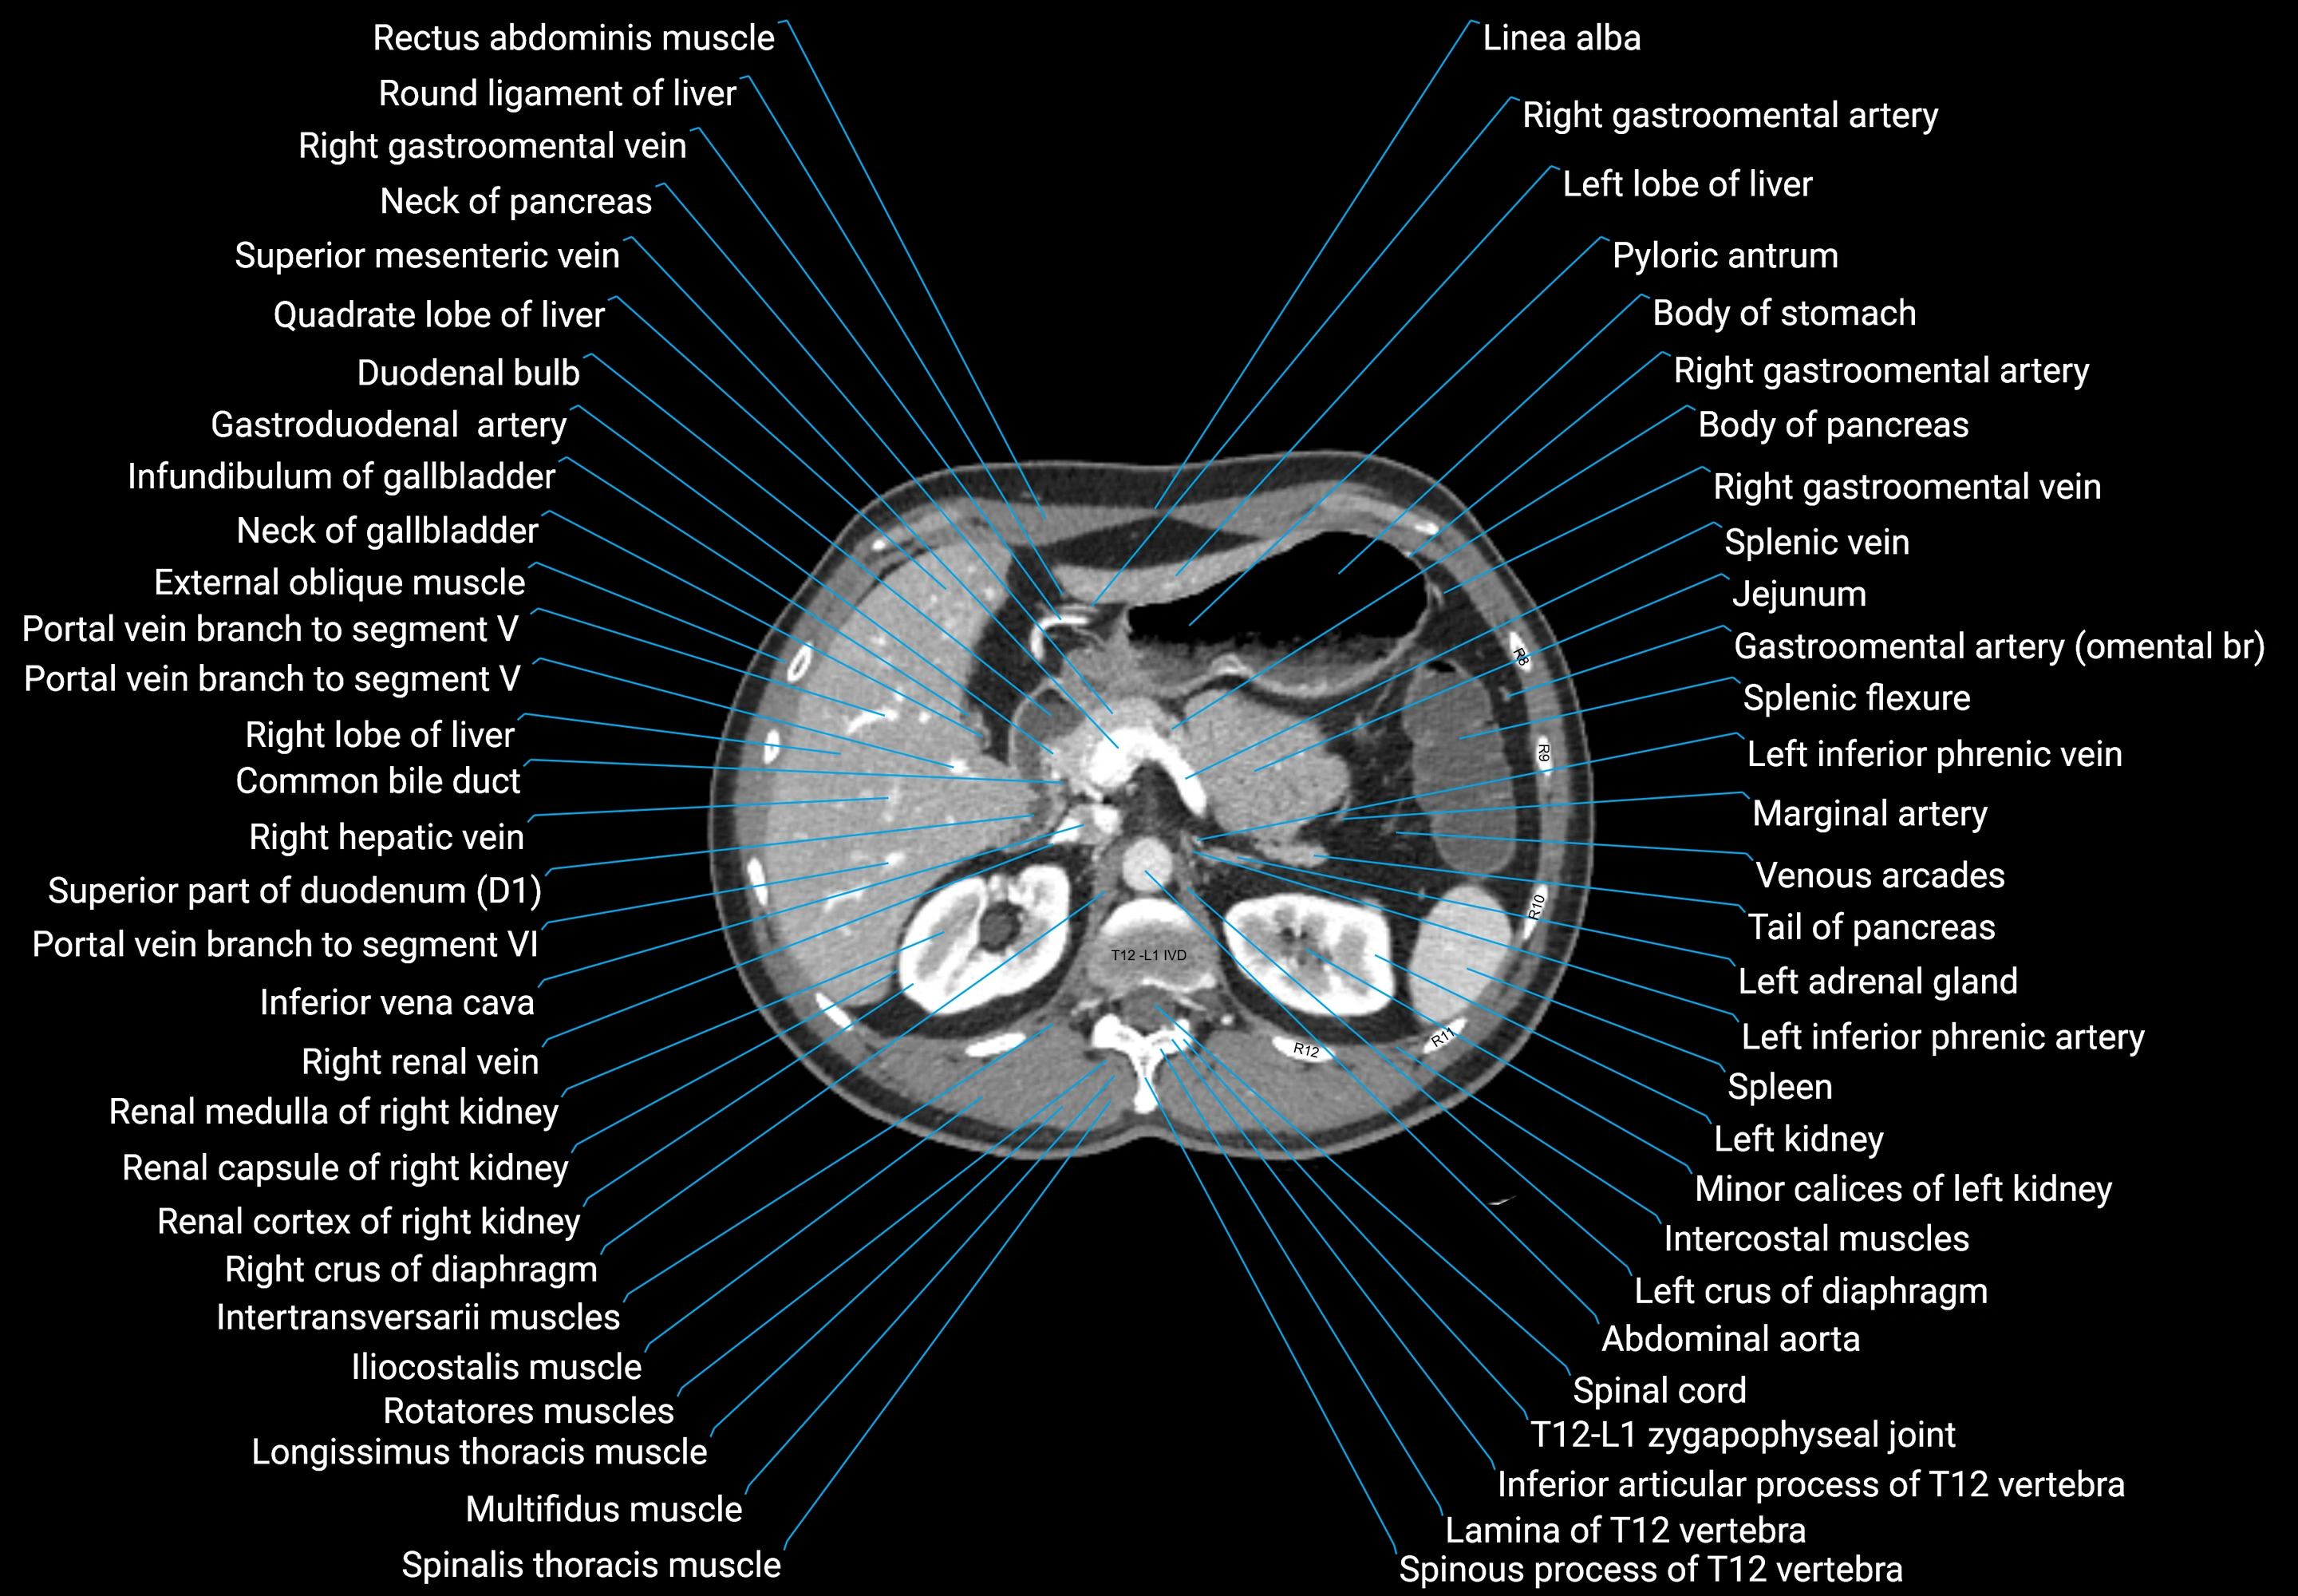

CT images